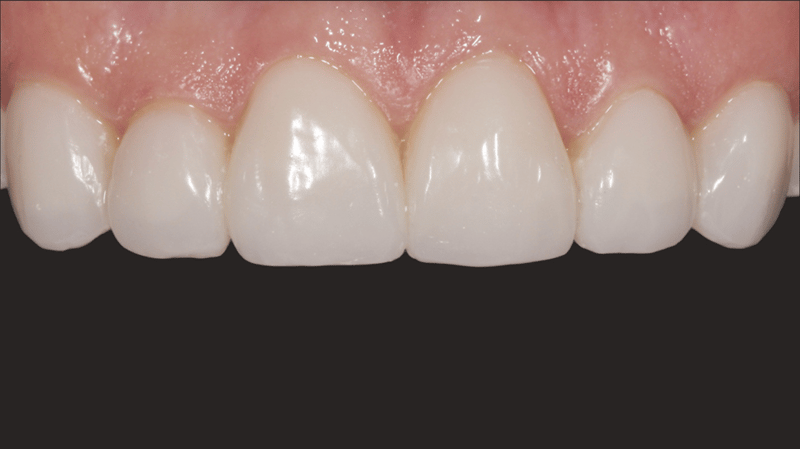

- Resultaat van het cementeren: De definitieve cementatie resulteerde in functionele, mooi aangebrachte veneers.

- Faciale anatomie: Voor het creëren van de faciale anatomie werd gebruikgemaakt van bolvormige en lange, dunne diamantboren. Met een gelobde diamantboor werden de lijnen van Retzius aangebracht. De eerste polijstbewerking werd gedaan met Jiffy™ Natural-polijstinstrumenten. De definitieve glans werd bereikt met Ultradent™ Diamond Polish Mint en de Jiffy™ Goat Hair Brush (niet beschikbaar in Europa), om de tertiaire anatomie niet te verwijderen.